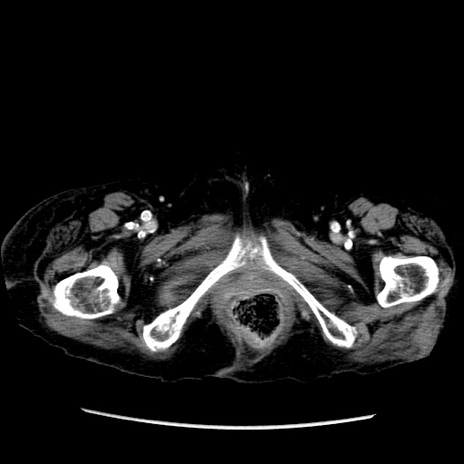

症例14(横断像)

【症例】 90歳代女性

【主訴】 腹痛・嘔吐

【現病歴】今朝から左側腹部痛を認めた。 経過観察していたが、嘔吐を認めたため来院。

【既往歴】 子宮癌術後

【身体所見】 意識清明、BP 127/54mmHg、P 98bpm Sp02 95%(RA)、BT 35.8°C、腹部平坦・軟腸ぜん動音聴取良好、右下腹部圧痛(+) 反跳痛なし

【データ】WBC 9800、CRP 0.46